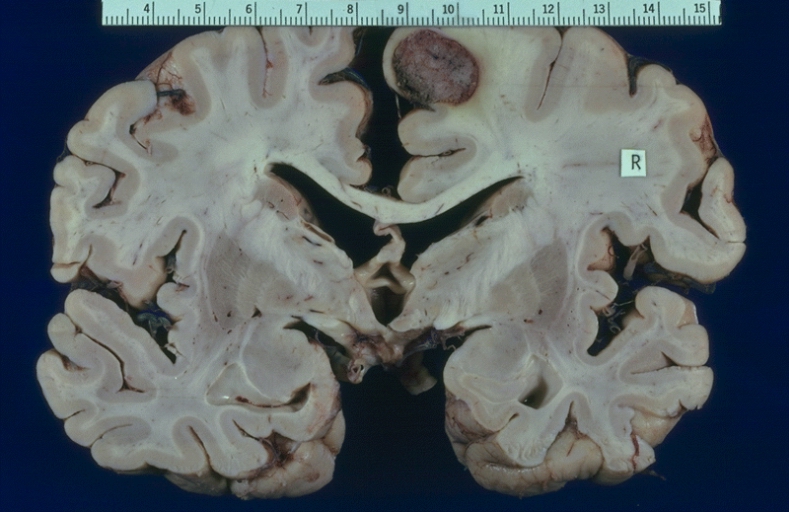

Photograph of acute middle cerebral artery (MCA) stroke. Image taken at autopsy on 10-24-2006 MODIFIED BACKGROUND

- MCA-Stroke-Brain-Human-2 © Marvin 101 is licensed under a CC BY-SA (Attribution ShareAlike) license